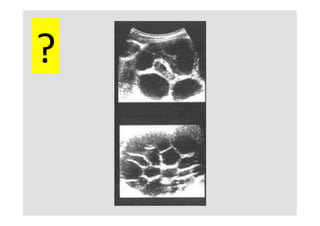

ClassificaKon	échographique

Gharbi

univésiculaire	 décollement	 mulKvésiculaire	 pseudotumoral	 calcifié

?